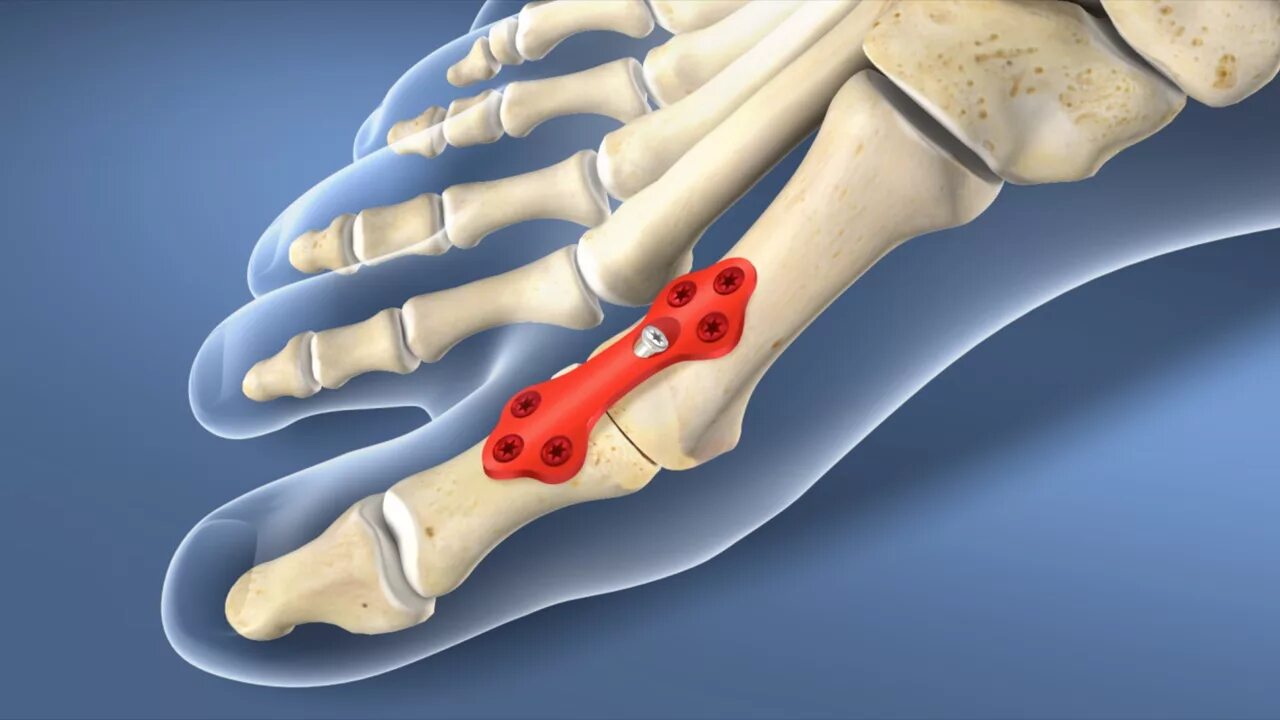

Остеоартрит 2025